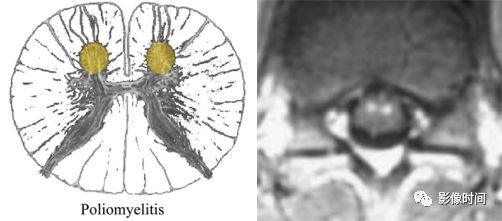

多发性硬化(Multiple sclerosis,MS)亦是一种严重的中枢神经系统自身免疫脱髓鞘病变,免疫球蛋白分泌 B 细胞和浆细胞的克隆性扩增,可使 CSF 中出现寡克隆带特征。

MRI:

脊髓:颈髓较常受累,病灶 T2WI 呈高信号,T1WI 呈稍低信号,轴位常分布于前索、侧索或者后索,长轴 ≤ 2 个连续阶段椎体,急性期呈斑片状、结节状或环形强化。

病灶位于侧索、长度小于3个椎体节段